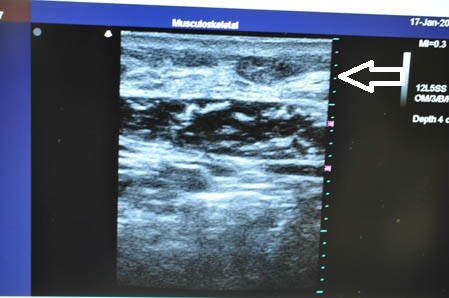

左腰。

↓ ↓ ↓

画像がしっかりと物語ってくれます。

きっちりと皮下脂肪を

根こそぎ!!

脂肪吸引しておきましたので